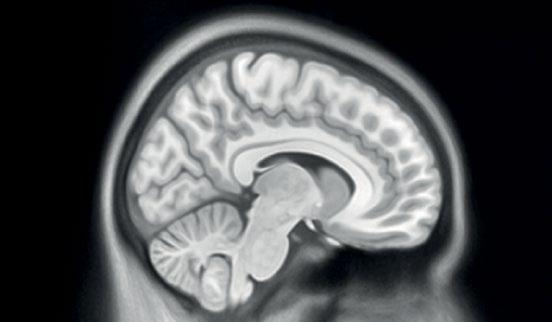

4 University of Luxembourg | LCSB | Imaging AI

Brain Cognition Data Embeddings” (ABCDE), it was conceived with Dr Marian van der Meulen from the Cognitive Neuroscience group at the Faculty of Humanities, Education and Social Sciences. It aims to integrate different types of biomedical data to study brain function and cognition. “We will transfer a widespread concept called embeddings and use it to combine image analysis with other markers,” explains Dr Andreas Husch. “Embeddings can be used to capture the relationships between different types of data. Just like some AI tools are now able to link sound, image, video and text, we want to do the same with functional MRI, blood markers and cognitive test scores.” By fusing these – originally quite incompatible – data thanks to recent machine learning and AI techniques, the researchers hope to create a solution to jointly analyse this assemblage for the first time. As brain imaging, cognitive scores and biomarkers form a combination that is highly relevant in neurodegenerative disorders like Alzheimer’s or Parkinson’s, the results could in the long term also help with predicting disease progression.

Imaging the brain: From a brain MRI to a digital 3D surface model to a sculpture in real life.